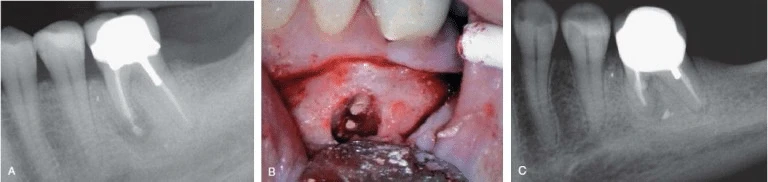

Hình 2. Chấn thương vật lý do chơi thể thao có thể gây nên nứt dọc chân răng. Đường nứt ở hình trên ở răng một trẻ 7 tuổi bị chấn thương do động kinh.

Hình 3. Nhiễm trùng tuỷ răng tái phát sau điều trị nội nha có thể là do nứt dọc chân răng